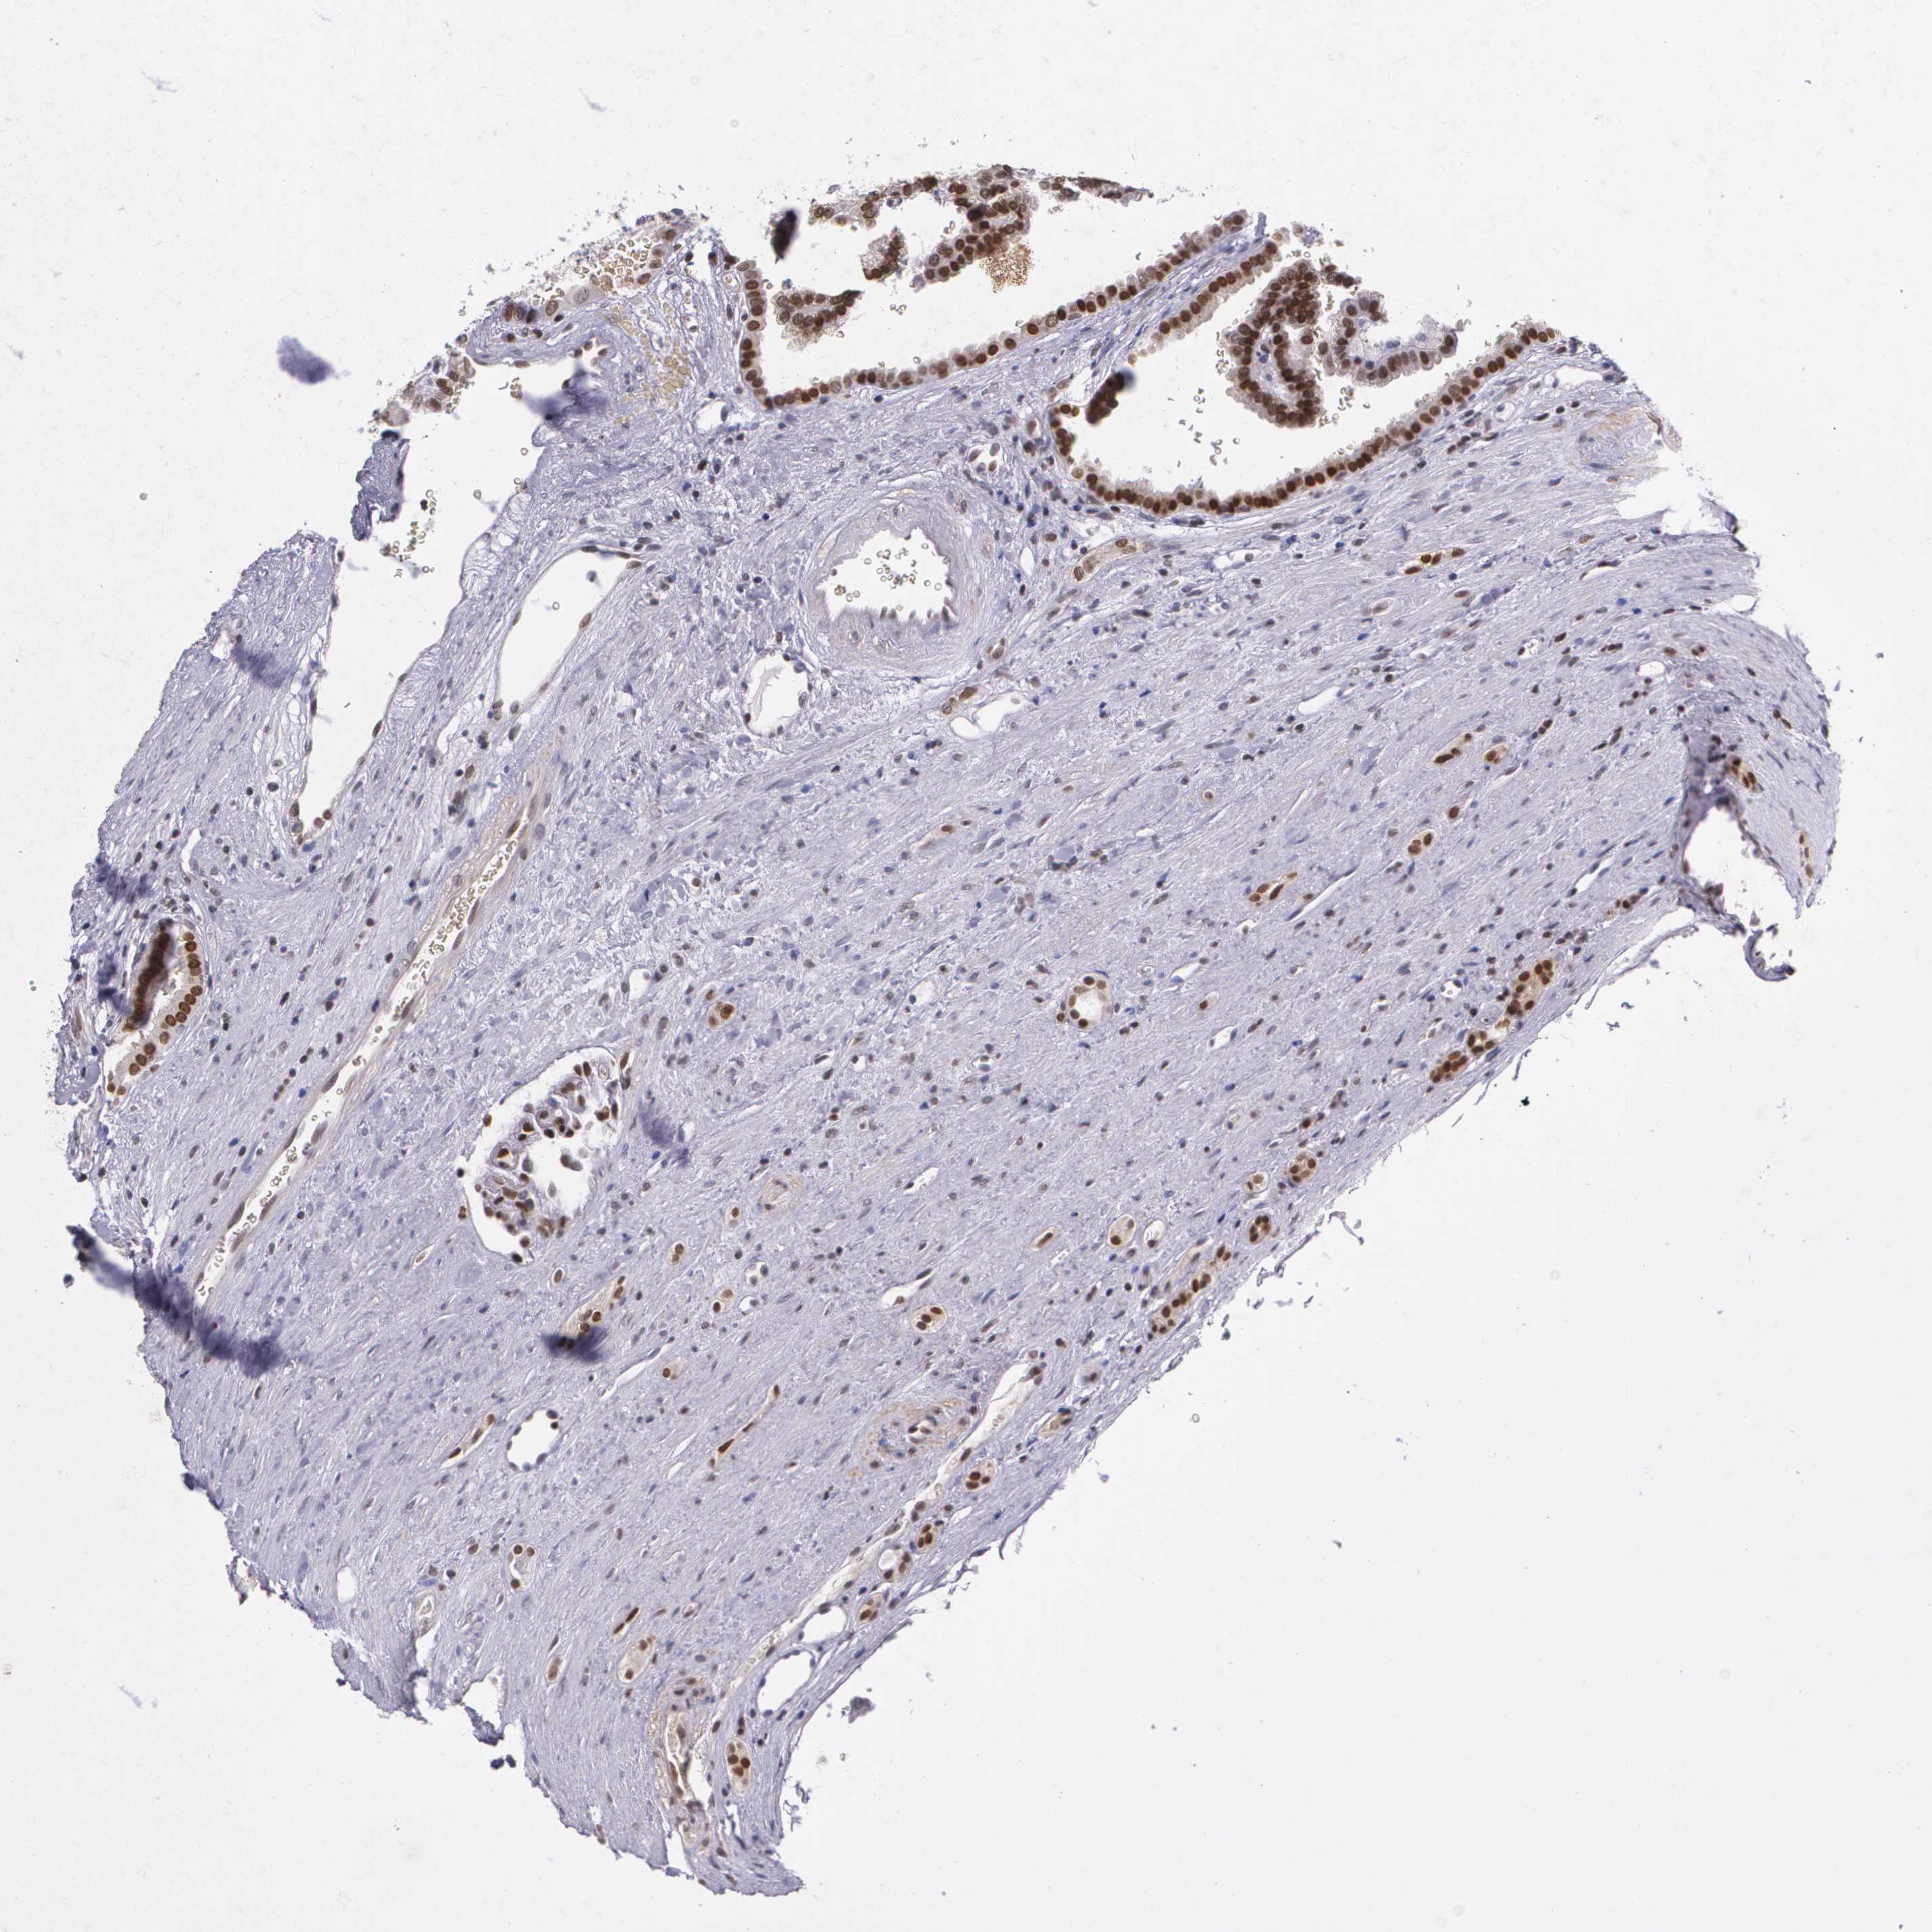

KIDNEY RENAL PAPILLARY CELL CARCINOMA (TCGA) - Interactive survival scatter ploti

The Survival Scatter plot shows the clinical status (i.e. dead or alive) for all individuals in the patient cohort, based on the same data that underlies the corresponding Kaplan-Meier plots. Patients that are alive at last time for follow-up are shown in blue and patients who have died during the study are shown in red.

The x-axis shows the expression levels (FPKM) of the investigated gene in the tumor tissue at the time of diagnosis. The y-axis shows the follow-up time after diagnosis (years). Both axes are complimented with kernel density curves demonstrating the data density over the axes. The top density plot shows the expression levels (FPKM) distribution among dead (red) and alive patients (blue). The right density plot shows the data density of the survived years of dead patients with high and low expression levels respectively, stratified using the cutoff indicated by the vertical dashed line through the Survival Scatter plot. This cutoff is automatically defined based on the FPKM cutoff that minimizes the p-score. The cutoff can be changed by dragging the vertical line or by entering a cutoff value in the square labeled "Current cut-off".

Under the Survival Scatter plot the p-score landscape (black curve; left axis) is shown together with dead median separation (red curve; right axis). Dead median separation is the difference in median mRNA expression between patients who have died with high and low expression, respectively. It is calculated as follows: median FPKM expression of dead patients with high expression - median FPKM expression of dead patients with low expression. This is intended to aid the user in visually exploring custom cutoffs and the associated p-scores and dead median separation.

Individual patient data is displayed and can be filtered by clicking on one or more of the category buttons on the top of the page. Categories describing expression level and patient information include: high, low, alive, dead, female, male and tumor stages. The scale of the x-axis can be toggled between linear and log-scale by clicking on the "x log" button. Mouse-over function shows TCGA ID, patient information and mRNA expression (FPKM) for each patient.

& Survival analysisi

Kaplan-Meier plots summarize results from analysis of correlation between mRNA expression level and patient survival. Patients were divided based on level of expression into one of the two groups "low" (under cut off) or "high" (over cut off). X-axis shows time for survival (years) and y-axis shows the probability of survival, where 1.0 corresponds to 100 percent.

MGMT is not prognostic in Kidney Renal Papillary Cell Carcinoma (TCGA)